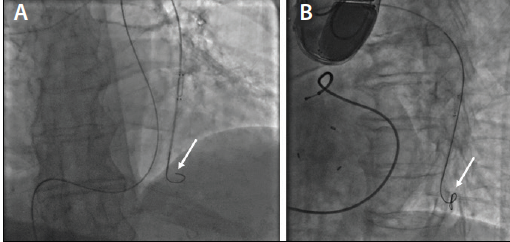

Figure 4. Sensor on the delivery catheter with fluoroscopic appearance of a distal wire loop. Removal of the wire with a distal wire loop may cause dislodgement of the senor to a more proximal location. Distal wire loop (arrow) (A). Distal wire loop (arrow) (B).

Once an appropriate implant location is identified, the delivery system is prepared by flushing the over-the-wire port with heparinized saline. The sensor and distal portion of the delivery catheter are agitated in heparinized saline for 20 to 30 seconds. A 0.018-inch wire is placed into the distal portion of the desired PA branch. Care should be taken to avoid creating a distal wire loop (Figure 4).

In the unlikely occurrence that the sensor is unable to traverse the inferior vena cava filter, a long 12-F sheath can be placed through the filter. Movement of the sensor to a more proximal location during deployment can be addressed by (1) maintaining distal wire position, (2) readvancing the inflated balloon wedge catheter to contact the sensor, (3) pushing the sensor forward using the inflated balloon wedge catheter, and (4) repeating this process until the sensor is advanced to the desired implant location. Snaring the sensor is not advised. Occasionally, a wire loop can form distal to the sensor (Figure 4), which could potentially engage the sensor during wire removal and potentially “pull” the sensor to a more proximal location. The most effective method to resolve a distal wire loop is to (1) release the sensor, (2) advance the delivery catheter past the sensor, (3) withdraw the distal portion of the wire with the wire loop into the delivery catheter, and (4) remove the delivery catheter and wire together to a location proximal to the sensor.